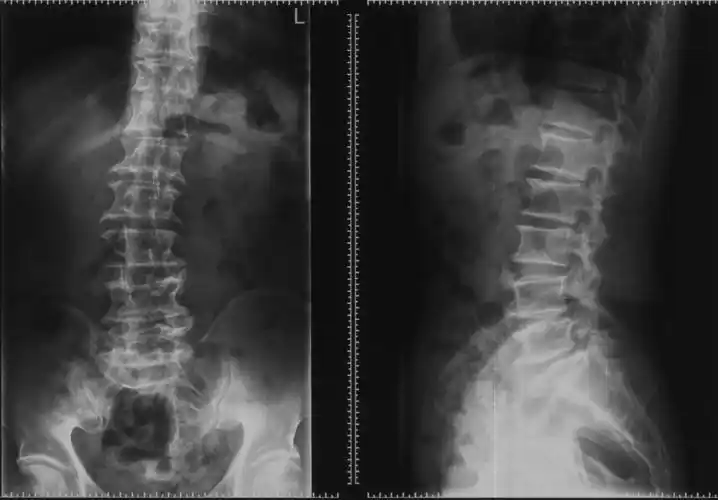

腰椎间盘突出症